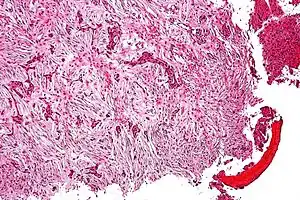

Adamantinoma ósseo é um tumor maligno de baixo grau, descrito por Fischer em 1913, acometendo pessoas da segunda e terceira décadas de vida, estando em 85% dos casos presente na tíbia. Cursa com metástase pulmonar de aparecimento tardio, da ordem de 15%.

Sua etiologia é ainda interrogada; estudos corroboram provavelmente com origem epitelial. O adamantinoma da mandíbula (hoje ameloblastoma) é originário da dentina, e viu-se que, apesar de parecido na histologia, é um tumor totalmente diferente do adamantinoma da tíbia.

A clínica é de dor insidiosa e massa palpável, porém 20% abrem com quadro de fratura patológica. Diferencia-se da displasia osteofibrosa por esta incidir em menores de 10 anos, ser indolor e totalmente intracortical. Na radiologia, o adamantinoma apresenta-se como múltiplas lesões líticas excêntricas acometendo grande área em diáfise da tíbia com contornos bem definidos. Inicia-se na cortical, mas invade medular. Pode ainda invadir a fíbula por contiguidade.